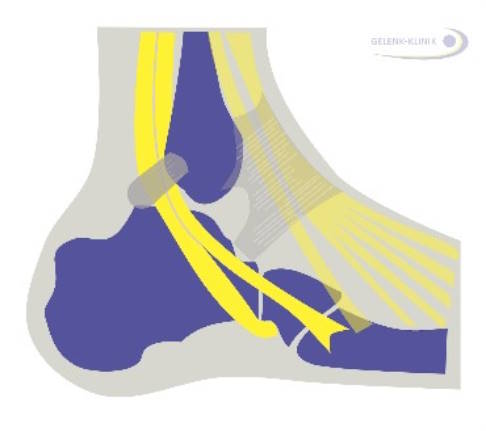

An jedem Bein gibt es zwei Peronealsehnen. Sie verbinden die beiden am äußeren Unterschenkel ansetzenden Wadenbeinmuskeln (Musculus peroneus longus und brevis, auch Musculus fibularis longus und brevis genannt) mit dem Fuß. Die kurze Peronealsehne zieht hinter dem Außenknöchel zum äußeren Fußrand und setzt am Mittelfußknochen V an. Die lange Peronealsehne verläuft in der gleichen Sehnenscheide ebenfalls um den Außenknöchel herum. Danach zieht sie unter dem Würfelbein (Os cuboideum) entlang Richtung Fußinnenrand. Dort setzt sie unterhalb der Basis des 1. Mittelfußknochens an.

Beide Sehnen liegen hinter dem Außenknöchel in einer knöchernen Gleitrinne, die anatomisch oft unterschiedlich geformt ist. Häufig ist sie flach oder sogar nach außen gewölbt. Ein Band aus Bindegewebe läuft vom Außenknöchel schräg nach hinten unten zum Fersenbein und sorgt dafür, dass die Sehnen nicht aus der Rinne heraustreten (luxieren).

Die Peronealsehnen übertragen die Kraft der Wadenbeinmuskeln auf den Fuß. Die kurze Peronealsehne zieht durch ihren Ansatz am Fußaußenrand den Fuß nach außen hinten und unterstützt die Pronation. Die lange Peronealsehne hat verschiedene Funktionen: Steht der Fuß auf dem Boden, richtet sie das Fußgewölbe auf und kippt den Rückfuß. Am herabhängenden Bein führt die Anspannung des M. peroneus longus zu einer Senkung des 1. Mittelfußknochens.

Zusammen wirken sie dadurch bei der Beugung (Plantarflexion) und der Pronation des Fußes mit und stabilisieren das obere Sprunggelenk. Bei einem plötzlichen Umknicktrauma ziehen sich die Peronealmuskeln als erstes zusammen, um den Knöchelbandkomplex zu stabilisieren. Sind die Peronealsehnen geschädigt, droht eine Instabilität des oberen Sprunggelenks.